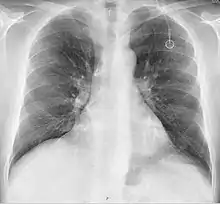

A follow-up on a chest radiograph can immediately detect complications associated with the procedure such as pneumothorax, hemothorax and malpositions of the catheter. However, routine chest radiography is not needed due to the low complication rates associated with the procedure. The chest radiograph is only done if there is clinical suspicion of a complication.[4]

The incidence of catheter fracture is 2.3%. The fracture can be due to "pinch-off syndrome" when the vein and the catheter is compressed when passes between the clavicle and first rib before turning 90 degrees into the superior vena cava. Fractured catheter component can dislodge most commonly into pulmonary arteries (35%), right atrium (27%), right ventricle (22%), and superior vena cava and peripheral veins (15.4%).[5]

- Pneumothorax: Attempts to gain access to the subclavian vein or jugular vein can injure the lung, potentially causing a pneumothorax. If the pneumothorax is large enough, a chest tube might need to be placed. In experienced hands, the incidence of this complication is about 1% when accessing the subclavian vein. When accessing the jugular vein the pneumothorax rate is virtually nonexistent.